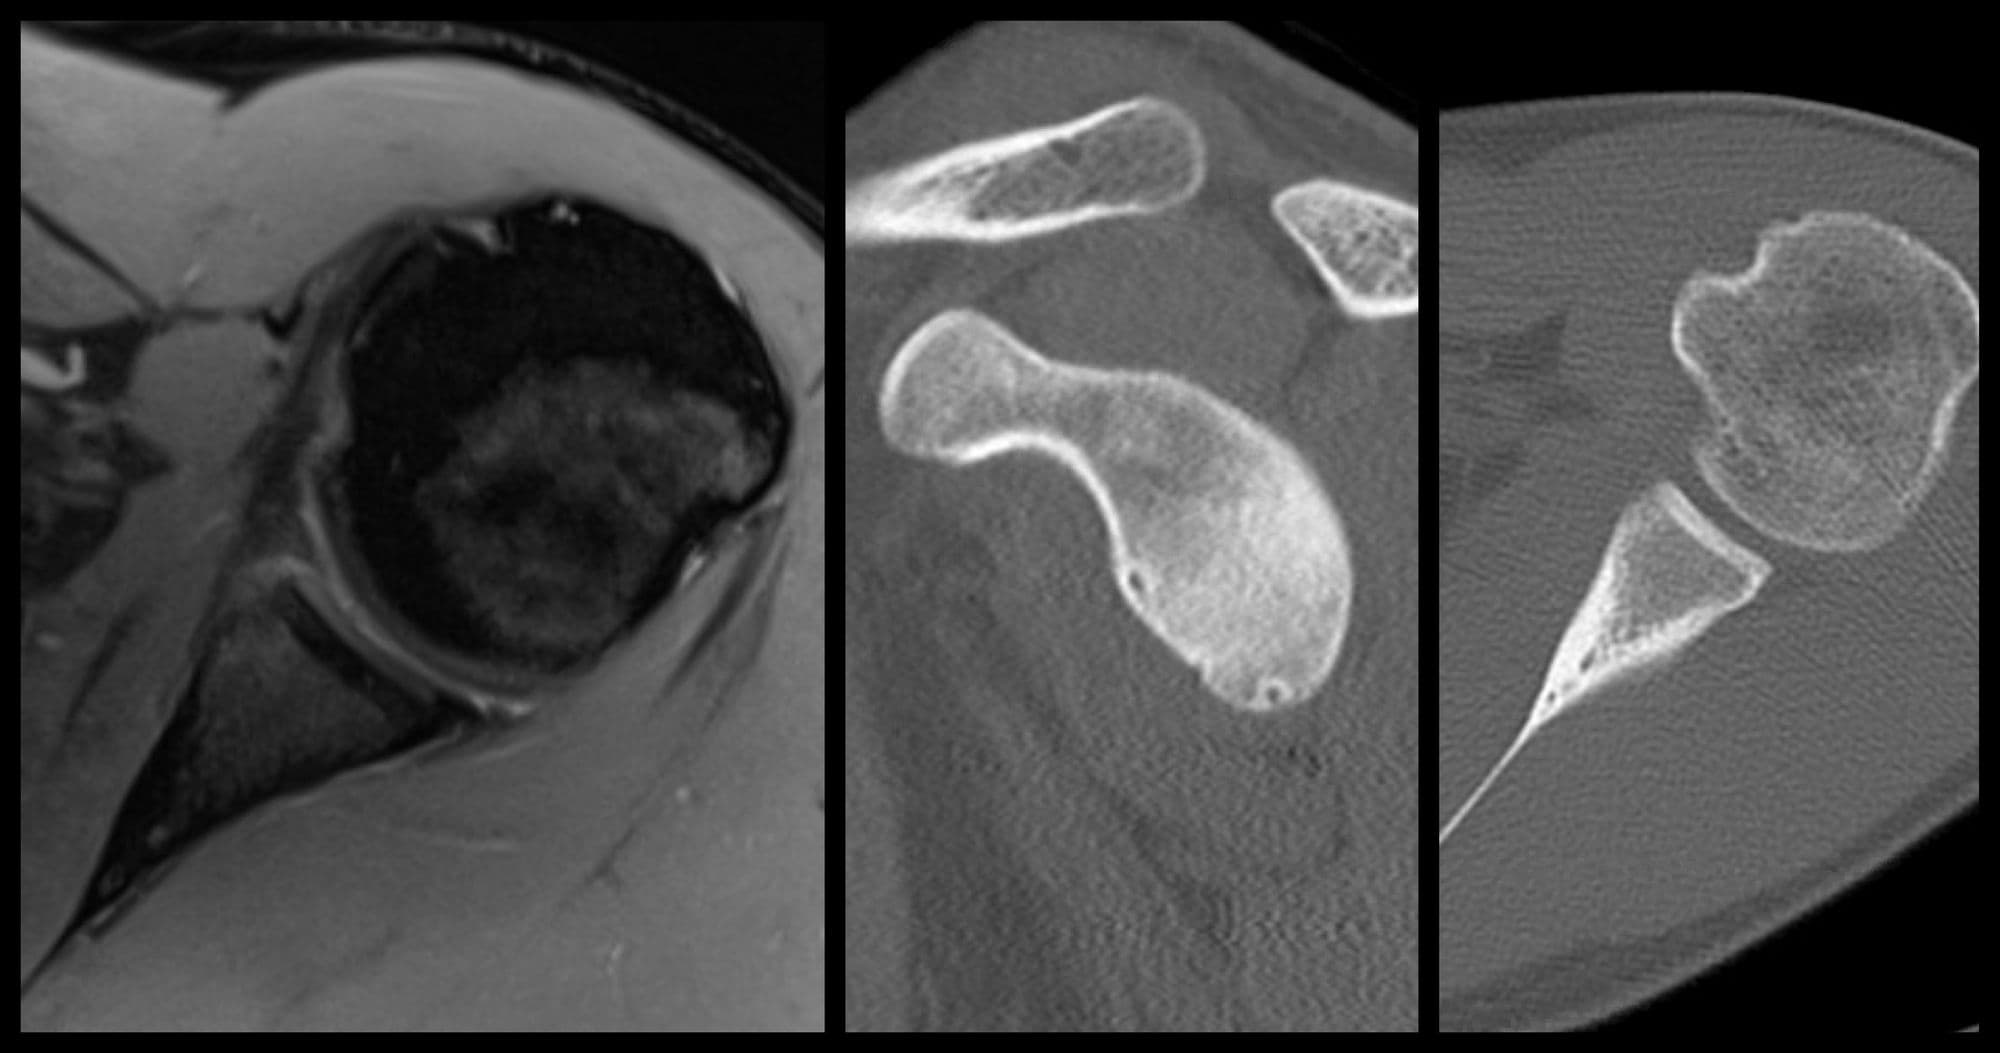

Glenoid Reconstruction with Allograft

Trauma UESports

Latarjet Procedure

Sports